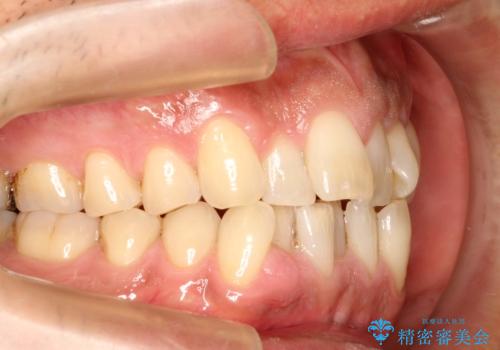

インビザライン invisalign ガタつきを治すマウスピース矯正

- 非抜歯・上顎臼歯遠心移動によるマウスピース矯正を計画した。

ガタつきを取り除くだけであれば非常に簡潔であるマウスピース矯正ですが、奥歯の位置関係の是正や、垂直的な歯の位置のコントロールなどが計画に含まれる場合、治療が難しくなってきます。